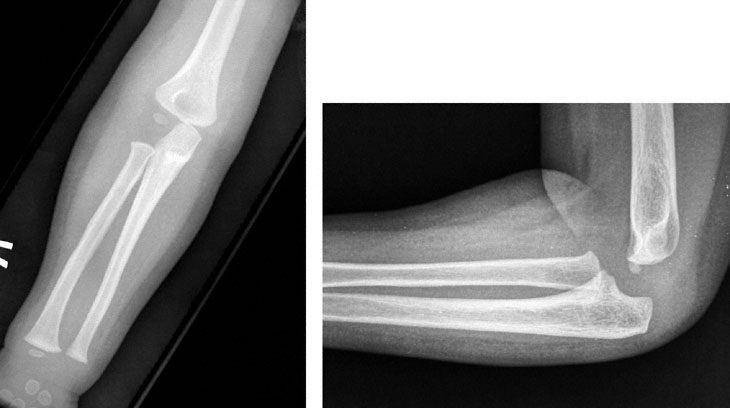

A 2-year-old girl is brought to the office by her father because of a 4-hour history of pain and decreased mobility in her right arm that began suddenly after her older brother swung her around by her arms. The father says, “I put ice on the arm and gave her ibuprofen, but she still won’t move it.” Growth and development have been normal. Vital signs are normal. The child is tearful. She holds her right arm flexed and pronated at her side. Physical examination of the right upper extremity shows no deformity, edema, or ecchymosis. Grip strength in the right hand is normal. Radial and ulnar pulses are strong bilaterally. X-rays of the right upper extremity are obtained and shown. Which of the following is the most appropriate initial management?